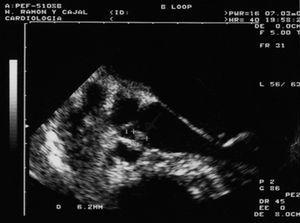

El paciente ingresó en la unidad de vigilancia intensiva de neurocirugía, donde fue valorado por el servicio de infecciosas. Por sus antecedentes, la presencia de petequias y múltiples estigmas de venopunción, y el cuadro neurológico agudo se solicitó ecocardiograma transtorácico urgente, con imagen indicativa de vegetación sobre válvula aórtica, que fue preciso confirmar con ecocardiograma transesofágico (fig. 2). Con el diagnóstico de endocarditis infecciosa se inició tratamiento parenteral con cloxacilina (2 g/4 h) y gentamicina (80 mg/8 h), sustituido a las 72 h por penicilina G sódica (4 MU/4 h) y gentamicina (80 mg/8 h) por aislamiento de Staphylococcus aureus sensible a penicilina en los hemocultivos del ingreso. En neurocirugía se decidió una actitud conservadora, por el alto riesgo quirúrgico, y no se llegó a realizar arteriografía. Una ecografía abdominal mostró esplenomegalia con imagen hipoecogénica en polo inferior sugestiva de infarto/hematoma. Tras deterioro clínico y radiológico (objetivado en una segunda TC realizada a las 72 h [fig. 3]), se produjo el fallecimiento del paciente en el cuarto día de ingreso, con el diagnóstico final de endocarditis infecciosa aórtica por S. aureus, complicada con embolismo esplénico y rotura de aneurisma micótico en el SNC como causa primera de la muerte, favorecida por coagulopatía y trombopenia multifactorial (VIH, VHC, sepsis).

Figura 2. Imagen del ecocardiograma transesofágico que muestra imagen de vegetación de 5 x 6 mm sobre cara ventricular de valva sigmoidea aórtica.